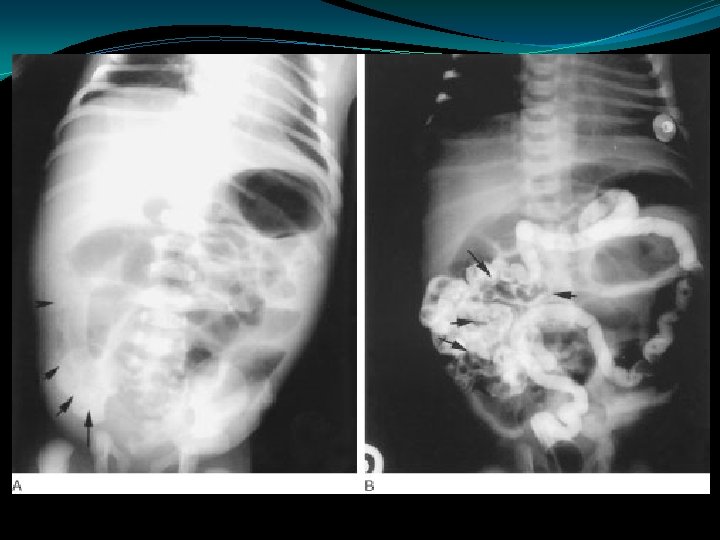

Malrotation/Volvulus Abdominal XRay �Normal film -20% �Dilated duodenal bulb and paucity of distal bowel gas �Double bubble sign �Distal gas filled bowel loops; gas filled volvulus (obstructed mesenteric veins prevent absorption of gas

Duodenal Atresia �Polyhydramnios �Partial obstructions: duodenal web, duodenal stenosis, annular pancreas � 40% of cases associated with trisomy 21 �Most common gut atresia in neonates �“Double bubble”